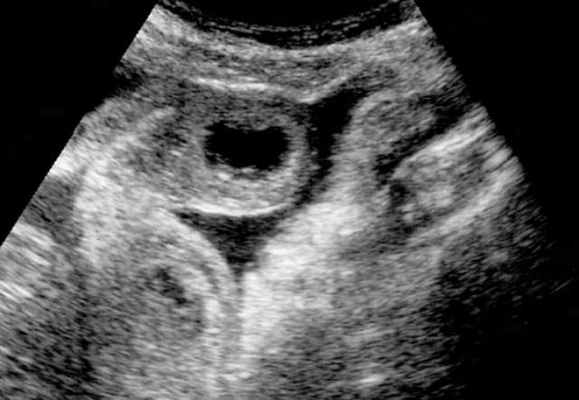

4. Ультразвуковое исследование (УЗИ) широко применяется для оценки разных болезней органов брюшной полости, однако исследований, посвященных диагностике КН, не много. Это может быть связано с тем, что наличие большого количества газа в ЖКТ мешает успешному исследованию кишечника, а также с тем, что спайки в кишке (наиболее распространенная причина кишечной непроходимости) не визуализируются с помощью УЗИ.

Предпосылкой возможного использования ультразвукового (УЗ) метода для диагностики ОКН является избыточное скопление жидкого содержимого в просвете кишки, что позволяет при УЗ-сканировании ее визуализировать.

Избыточное скопление жидкости в кишечнике обусловлено как нарушением эвакуации и всасывания кишечного содержимого, так и пропотеванием жидкости в просвет кишки при развитии ее микроциркуляторных нарушений. В связи с этим жидкое содержимое в просвете кишки, определяемое при УЗИ, называют «симптомом секвестрации жидко

Современные подходы диагностики включают в себя УЗИ брюшной полости или рентгенографию в положении стоя- как первая линия визуализации. В последнее время наблюдается повышенная тенденция использования УЗ-метода, который, как считают некоторые авторы, может заменить классическую рентгенографию. УЗИ позволяет корректно определить наличие тонкокишечной обструкции, при этом зачастую выявляет много рaзличной дополнительной диагностической информации, имеющей определяющее значение для лечебной тактики.

УЗД признаки тонкокишечной непроходимости

Основные УЗ-признаки при непроходмости- это визуализация расширенных петель тонкой кишки, сниженная перистальтика, свободная жидкость между петлями (танга) и в брюшной полости. Также УЗИ иногда позволяет обнаружить причину обструкции, например, опухоль, утолщение стенок терминального сегмента подвздошной кишки при болезни Крона и т.д. УЗИ может решить диагностическую дилемму при неоднозначных рентгенологических признаках на обзорной рентгенограмме брюшной полости. Лимит метода заключается в низкой специфичности при оценки состояния брыжейки, а также зависимость качества диагностики от конституции пациента и опыта оператора.

примеры сонограмм с расширенными петлями тонкой кишки

УЗИ позволяет прекрасно лоцировать свободную жидкость в брюшной полости